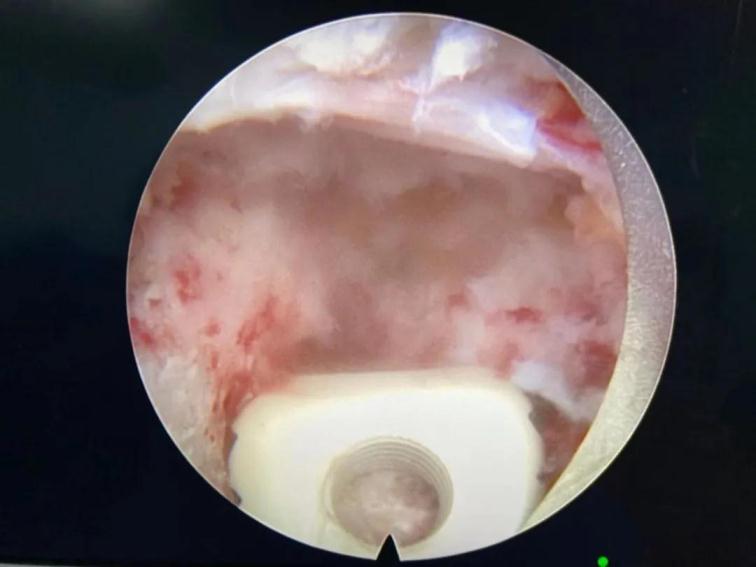

鏡下椎間融合

與傳統(tǒng)的腰椎后路開放減壓手術(shù)及通道下的MIS-TLIF手術(shù)相比,經(jīng)脊柱內(nèi)鏡后路腰椎ENDO-TLIF手術(shù),創(chuàng)傷更小,神經(jīng)根及硬膜囊顯露清晰,且最大限度的保護(hù)了脊柱骨骼、韌帶及肌肉的完整性,對(duì)脊柱運(yùn)動(dòng)單元穩(wěn)定性影響較小,術(shù)后患者感受更佳,康復(fù)更快。目前,該患者術(shù)后癥狀消失,已經(jīng)能夠行走自如,對(duì)治療效果非常滿意。